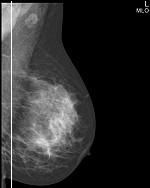

◄ прямая проекция (кранио-каудальная) – CC (КК)

◄ косая проекция (медио-латеральная) – MLO (МЛК)